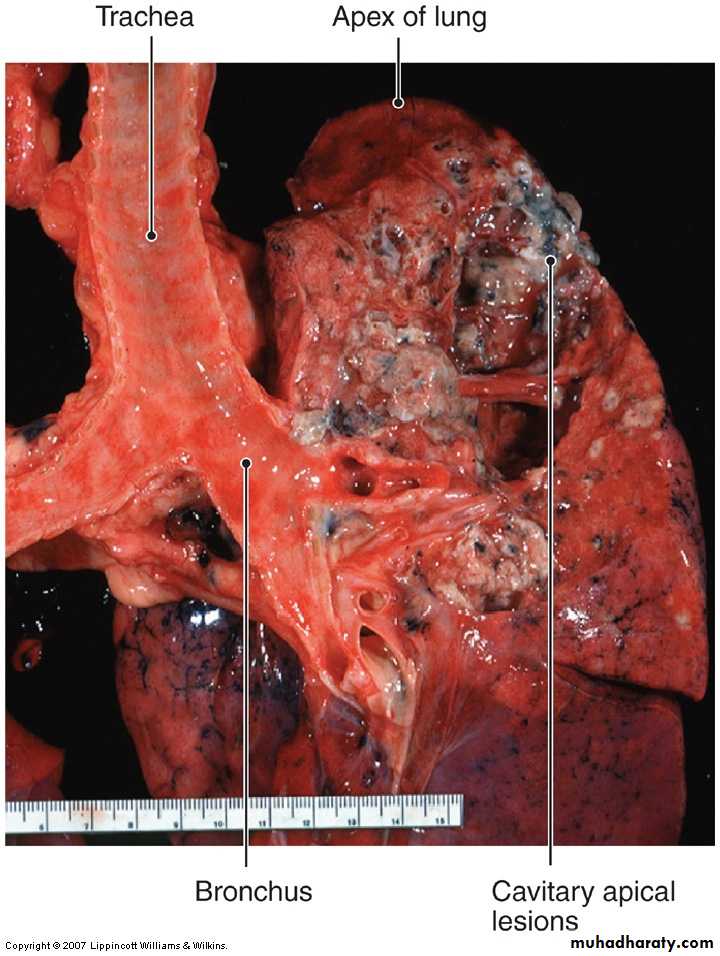

Tuberculosis

Mycobacterium tuberculosisChronic granulomatous inflammation with caseous necrosis

Chronic pneumonia is most often a localized lesion in an immunocompetent person, with or without regional lymph node involvement. There is typically granulomatous inflammation, which may be due to bacteria (e.g., M. tuberculosis) or fungi.

While in the immunocompromised, such as those with debilitating illness, on immunosuppressive agents, or with human immune deficiency virus (HIV) infection , there is usually systemic dissemination of the causative organism, accompanied by widespread disease. Tuberculosis is by far the most important entity within the spectrum of chronic pneumonias